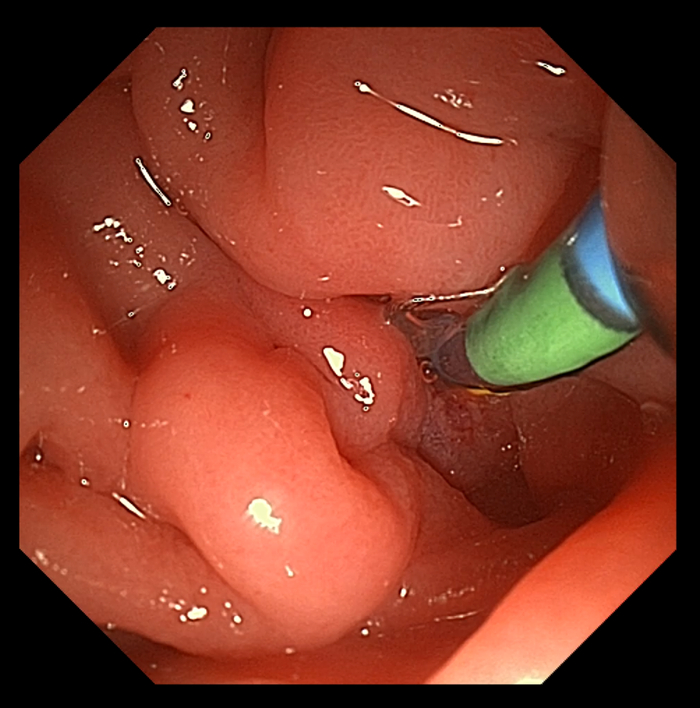

患者男,65岁。于十二指肠内侧找见主乳头,乳头呈鼻型,开口呈绒毛样。胆管狭窄导致反复超选导丝无法进入,后使用一次性粘膜切开刀,沿胆管方向行预切开,再次插管导丝进入胆管,注入少量造影剂,胆管显彰。

患者于三月后更换胆管支架,十二指肠镜应用操作如图所示:

术后,王雷教授表示道,澳华全新一代UHD-ED300V十二指肠镜在4K超高清内镜系统AQ-300的加持下,即使是面对高度复杂的ERCP手术也不在话下。

在高分辨率之下,可为医生提供更加清晰的观察条件,助力辨认十二指肠的异常病变、快速找到十二指肠乳头,利于医者更加精准迅速做出正确决策,为患者提供更安全、有效的治疗体验。